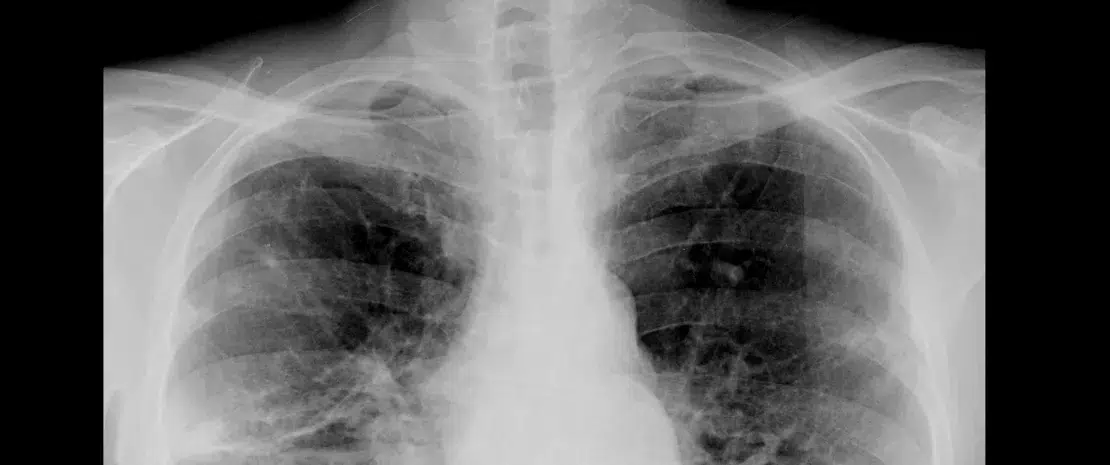

La broncho-pneumopathie chronique obstructive (BPCO) touchait en 2010 3,5 millions de personnes en France. Elle est responsable de plus de 100 000 hospitalisations par an pour des exacerbations aiguës (EA)*. Ces épisodes sont associés à une augmentation de la mortalité à court et moyen termes. Des études ont montré une réduction de la diversité du microbiote pulmonaire chez les patients atteints de BPCO, et évoqué une possible responsabilité de cette dysbiose dans l’inflammation des voies aériennes et l’affaiblissement de l’immunité locale.